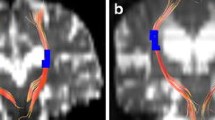

Measurement of LVV and GFA maps of a typical iNPH patient and the reconstruction results of bilateral C_PH, left CST, and left TRP. (A) Measurement of LVV of a typical iNPH patient. Green and blue indicate the right and left lateral ventricles, respectively. (B, C, and D) GFA maps and reconstruction results of bilateral C_PH, left CST, and left TRP of a typical iNPH patient. (B) Colour bar from 0 (black) to 0.2 (white); red, purple, yellow, and green indicate the range of the right C_PH, left C_PH, left CST, and left TRP, respectively. (C and D) Reconstruction results of the bilateral C_PH, left CST and left TRP

Our team explored white-matter abnormality patterns in iNPH compared to controls along with tract analysis based on DSI, such as the coexistence of increased and decreased FA or GFA in different segments of CST and TRP, as well as the decreased FA or GFA and impaired fibre integrity throughout C_PH [13]. In this study, the effect of ventricular enlargement on periventricular white matter fibre tracts was polarising; that is, the FA or GFA of certain fibre tracts increases or decreases simultaneously with ventriculomegaly, and FA values heterogeneity may be related to the coexistence of two different pathological processes: neurodegeneration (decreased FA) and ventricular expansion (increased FA) [28]. GFA is similar to FA and reflects changes in fibre tract integrity. In the brain, FA values are influenced by the diameter, density, and nerve fibre myelin formation extent. According to previous studies, enlarged lateral ventricles mechanically compress axons in the CST, causing water molecules to align along the axons, which leads to increased FA values [29, 30]. Our finding of elevated FA or GFA in the localised left CST and bilateral TRP segments with increasing ventricular volume confirmed this. The CST projects fibres through the posterior limb of the IC, through which the CST is connected to the cerebral cortex and controls somatic movements. The thalamic radiation posterior comprises fibre tracts from the thalamus to the occipital lobe, the local anatomical arrangement of which is closely related to the lateral ventricle [23].